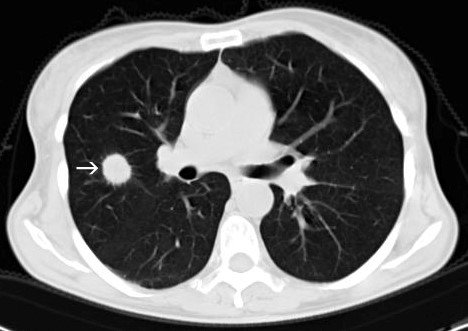

Görüntüləmə müayinəsində ağciyər parenximası daxilində tapılan təksaylı, asimptomatik düyünə deyilir. Ağciyərdə tapılan törəmələr ölçüsünə görə belə adlanır:

- düyün – ölçüsü 3 sm-dən kiçik törəmələrə deyilir

- kütlə – ölçüsü 3 sm-dən böyük törəmələrə deyilir (bədxassəlilik ehtimalı yüksəkdir).

Təksaylı düyünlərin əksəriyyəti (90%) xoşxassəlidir.

- Rentgenoloji müayinədə və ya KT-də ağciyər periferiyasında dairəşəkilli düyün var, digər patologiyalar (plevral maye, limfadenopatiya, atelektaz) yoxdur.

İlk növbədə törəmənin solitar düyün olduğu araşdırlır. Bunun üçün klinik əlamətlər araşdırılır və incə kəsiklərlə (1 mm) KT edilir.

Pulmonar və digər klinik əlamətlər yoxdursa, törəmənin ölçüsü 3 sm-dən kiçikdirsə, parenxima daxilində yerləşmişsə və digər patologiyalar (plevral maye, atelektaz, limfadenopatiya) tapılmırsa solitar ağciyər düyünü kimi qəbul olunur.